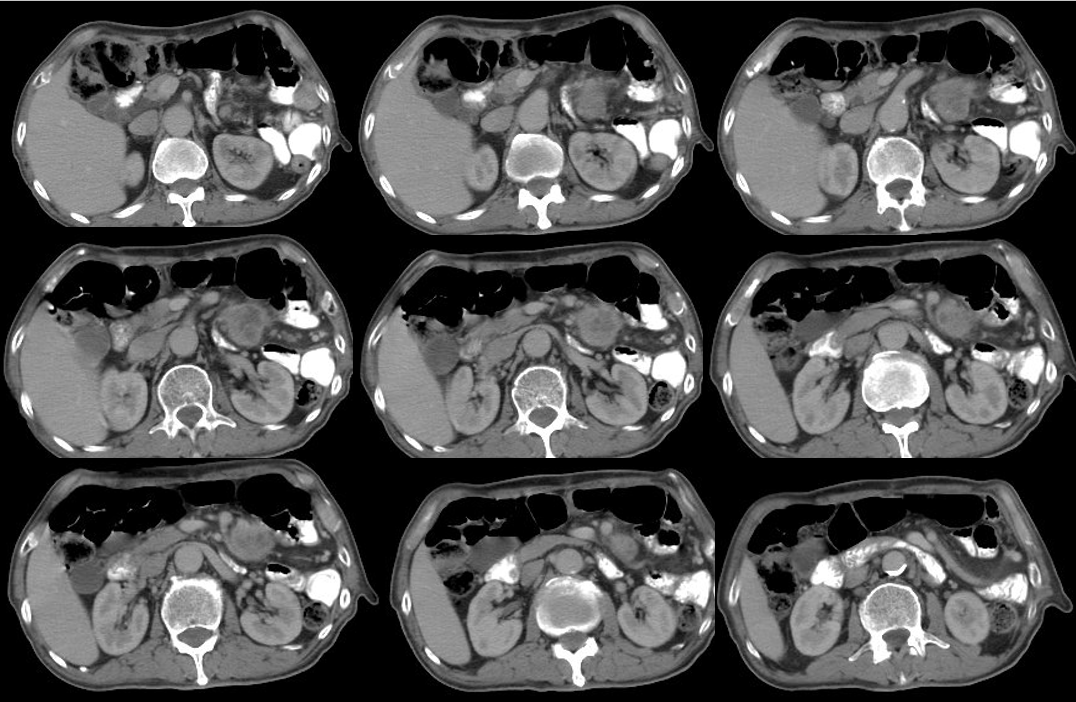

2018-10-09 食管中下段管壁增厚

2018-10-09左上腹系膜区结节灶